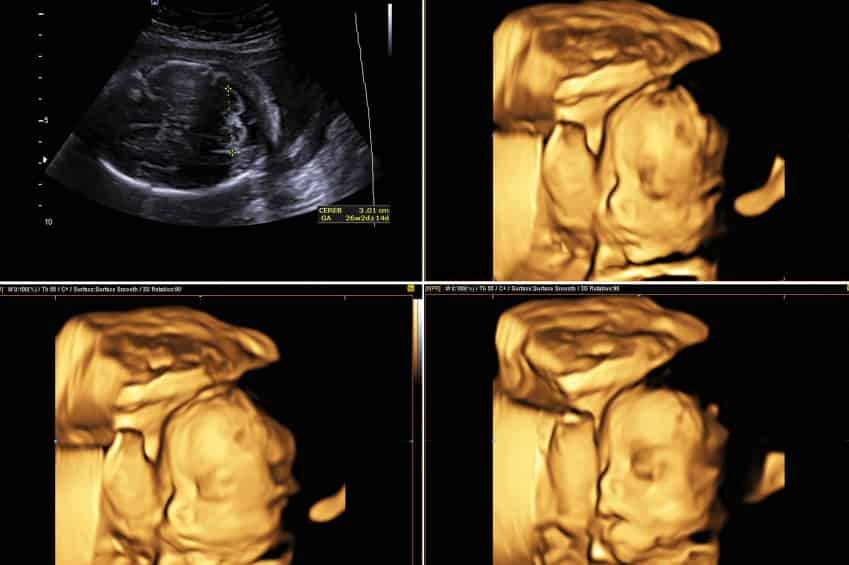

Tão seguro quanto qualquer outro tipo de ultrassom, no ultrassom 4D é possível ver o bebê se movimentando em tempo real, além de vê-lo em três dimensões diferentes. Através de um software, as imagens capturadas em 3D são agrupadas para que os movimentos do bebê possam ser vistos com nitidez durante o exame. Ainda, o ultrassom 4D consegue ajudar os médicos a avaliarem, com mais precisão, o volume e o funcionamento dos órgãos, como o coração e o pulmão.

Muito mais do que ver o bebê em tempo real, as imagens obtidas com o ultrassom 4D são mais nítidas e, consequentemente, possuem melhor qualidade, proporcionando um momento único para os ansiosos papais. O ultrassom 4D consegue mostrar traços bem definidos do rosto, pés e mãos do bebê, por exemplo. Além do mais, ele consegue trazer mais segurança, pois permite que os pais possam ver que o bebê está se desenvolvendo bem durante a gestação. Por conta disso, o ultrassom 4D vem sendo cada vez mais procurado.

Por se tratar de um vídeo em tempo real, e dependendo da fase de desenvolvimento e da posição do bebê na barriga da mãe, é possível ver movimentos como um bocejo, sorrisos, olhar, piscar de olhos, o ato do bebê colocar a mão na boca e até os movimentos de sucção podem ser vistos no ultrassom 4D. Ainda, caso os pais desejem, há a possibilidade de pedir a gravação do exame, para que eles possam assisti-lo, e até mostrar para a criança, sempre que desejarem. Afinal, este será um momento único.

Para fazer o ultrassom 4D, a melhor época é entre 26 e 30 semanas da gravidez. Nesse tempo, o bebe já começa a chupar o dedo e fazer movimentos de sucção com a boca, suas pálpebras não estarão mais coladas, e ele já pode abrir e fechá-las normalmente. Além disso, ele também estará desenvolvendo a capacidade de ver e ouvir, e nisso, é possível perceber que ele fica sensível aos estímulos do ambiente, como ruídos e música, por exemplo. Ou seja, é nessa fase que o exame pode proporcionar experiências únicas para os pais com o bebê ainda na barriga.